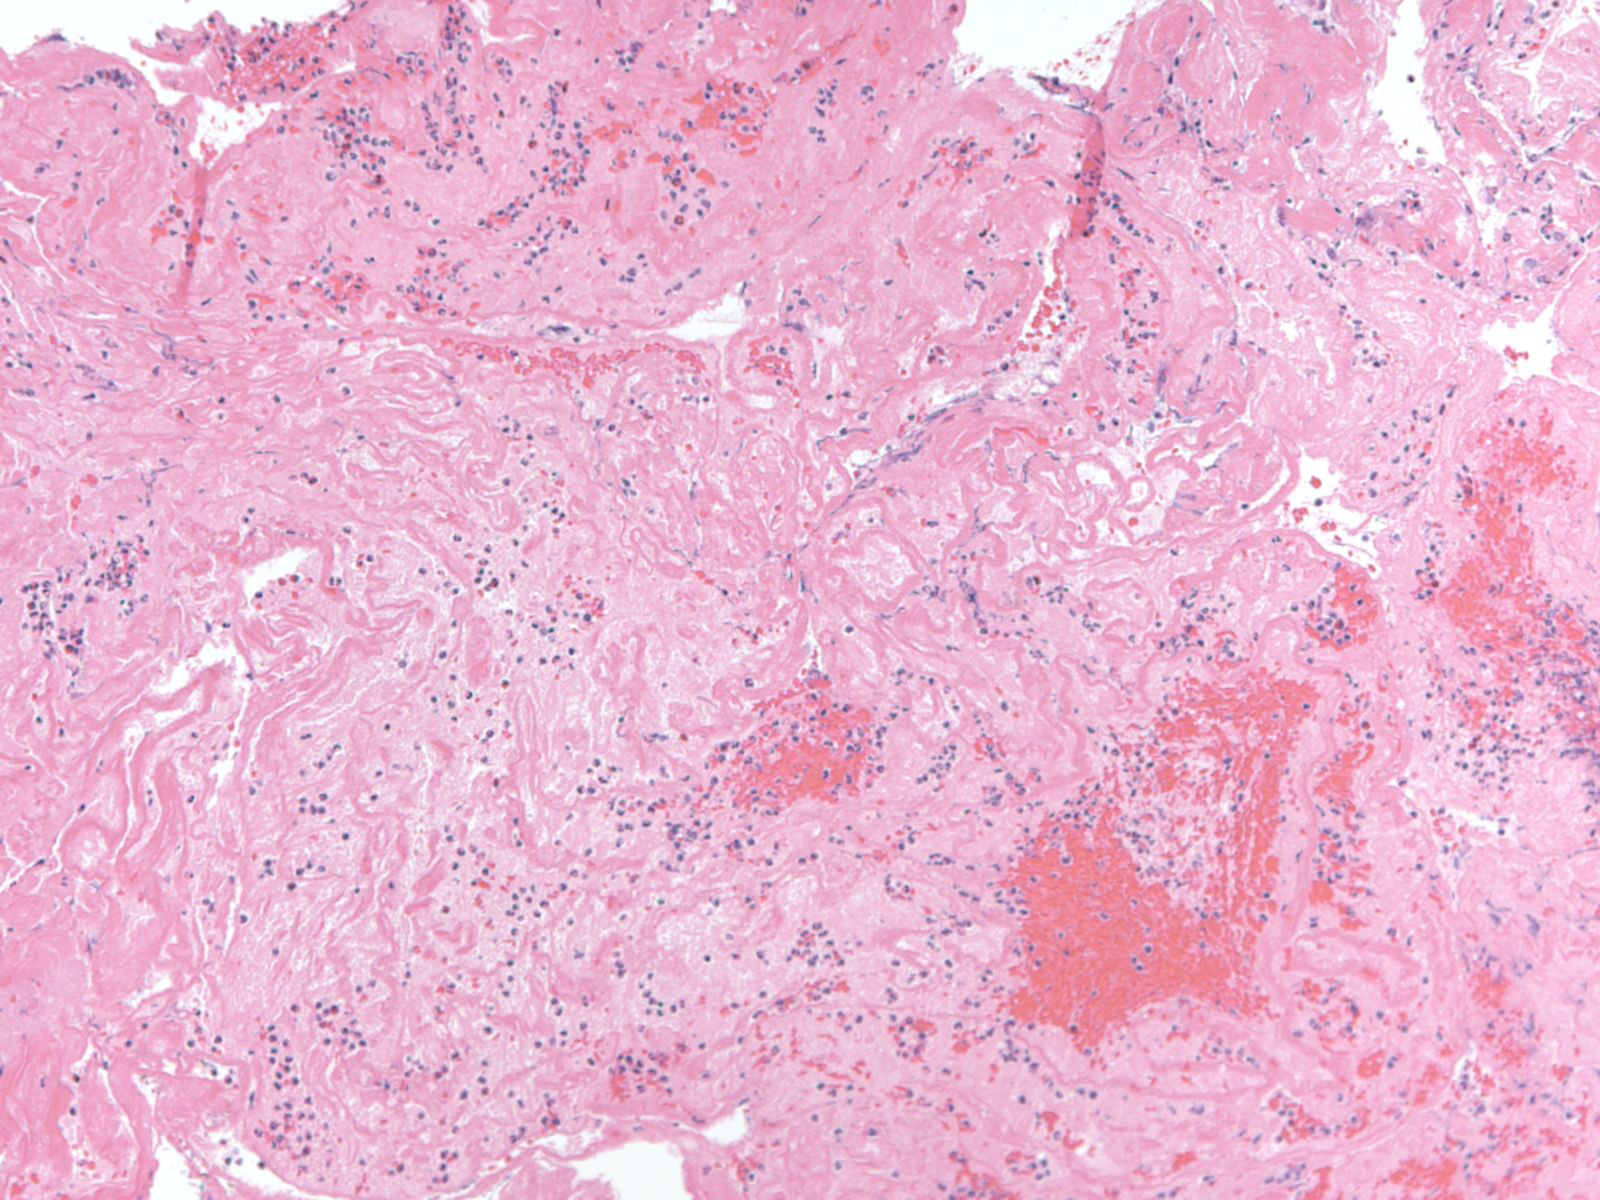

The patient was then taken urgently to the interventional radiology suite for mechanical thrombectomy of the left M2 thrombus. Using a 4mm x 15mm Solitaire stent-retriever TICI 3 flow was established after one pass (Figure 3). Thrombus on gross appearance appeared fibrinous. Microsopic evaluation of the thrombus showed a fibrin blood clot composed of multiple overlapping layers of fibrin admixed withplatelets, rare pools of red blood cells, and neutrophils, as can be seen in thrombus formed within 72 hours (Figure 4).

Figure 4 100x view of H&E section of aspirated thrombus. There are overlapping layers of fibrin admixed with platelets and rare pools of red blood cells admixed with neutrophils seen on this section.